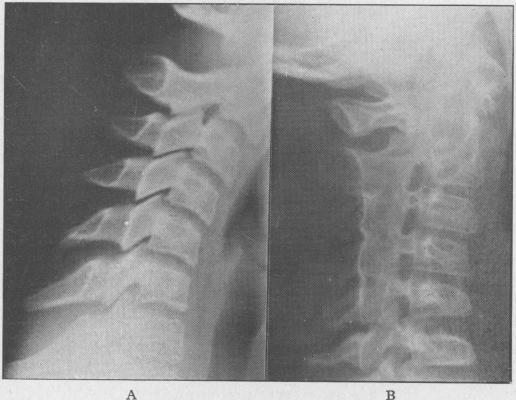

Juvenile rheumatoid arthritis (Still's disease).